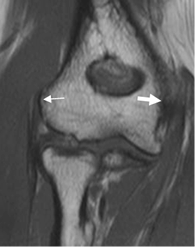

Fig 8. Lesión osteocondral

A: Rx AP. Osteopenia difusa por artritis reumatoidea, con disminución de los espacios articulares.

B: RM coronal en T1 y C: RM coronal en STIR. Lesión osteocondral del epicóndilo lateral, con erosión y alteración de la señal.